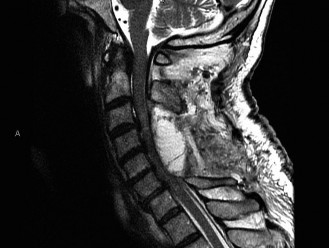

To evaluate the neural elements and the soft tissue structures, a comprehensive MRI of the lumbar spine without contrast was obtained. The T2-weighted sagittal and axial sequences confirmed the Grade 2 anterolisthesis and demonstrated severe bilateral foraminal stenosis at L5-S1. The exiting L5 nerve roots were severely compressed between the hypertrophied, fibrocartilaginous pseudarthrosis tissue of the pars defect dorsally, and the bulging, degenerated L5-S1 disc and superior endplate of S1 ventrally. Furthermore, the MRI revealed Modic Type II changes (fatty replacement of the subchondral bone marrow) in the adjacent vertebral endplates, confirming chronic biomechanical stress and discogenic degeneration. The central canal remained relatively patent, which is characteristic of isthmic spondylolisthesis, as the posterior neural arch is left behind during the anterior translation of the vertebral body.

Clinical & Radiographic Imaging Archive